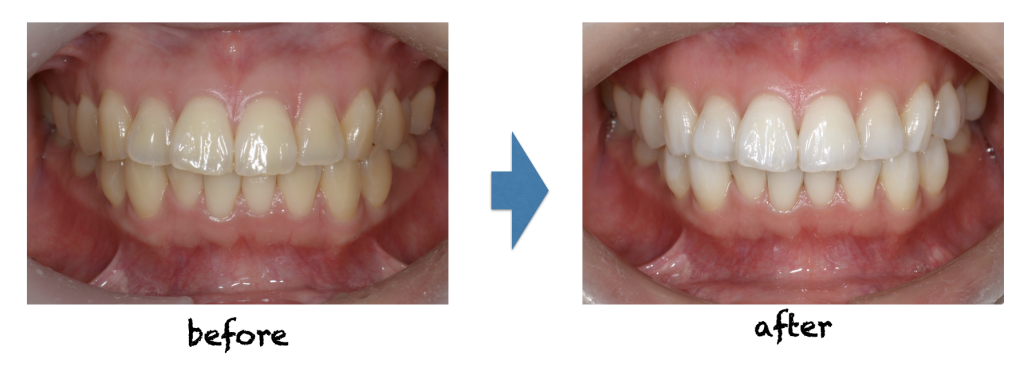

「最近、歯の黄ばみが気になる」「マスクを外したときの印象を良くしたい」そんなお悩み、ありませんか? 歯の色は、加齢や飲食、生活習慣によって少しずつ変化していきます。ホワイトニングは、専用の薬剤を使って